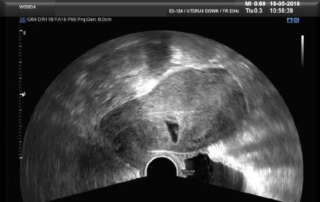

Description of the Endometrium at the different phases of the Menstrual Cycle (A Handout)